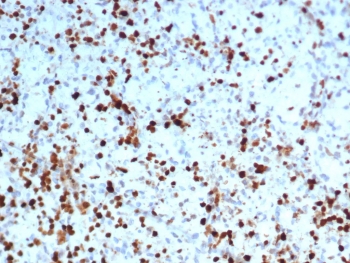

IHC staining of FFPE human spleen tissue with S100A4 antibody (clone S100A4/7096). HIER: boil tissue sections in pH 9 10mM Tris with 1mM EDTA for 20 min and allow to cool before testing.